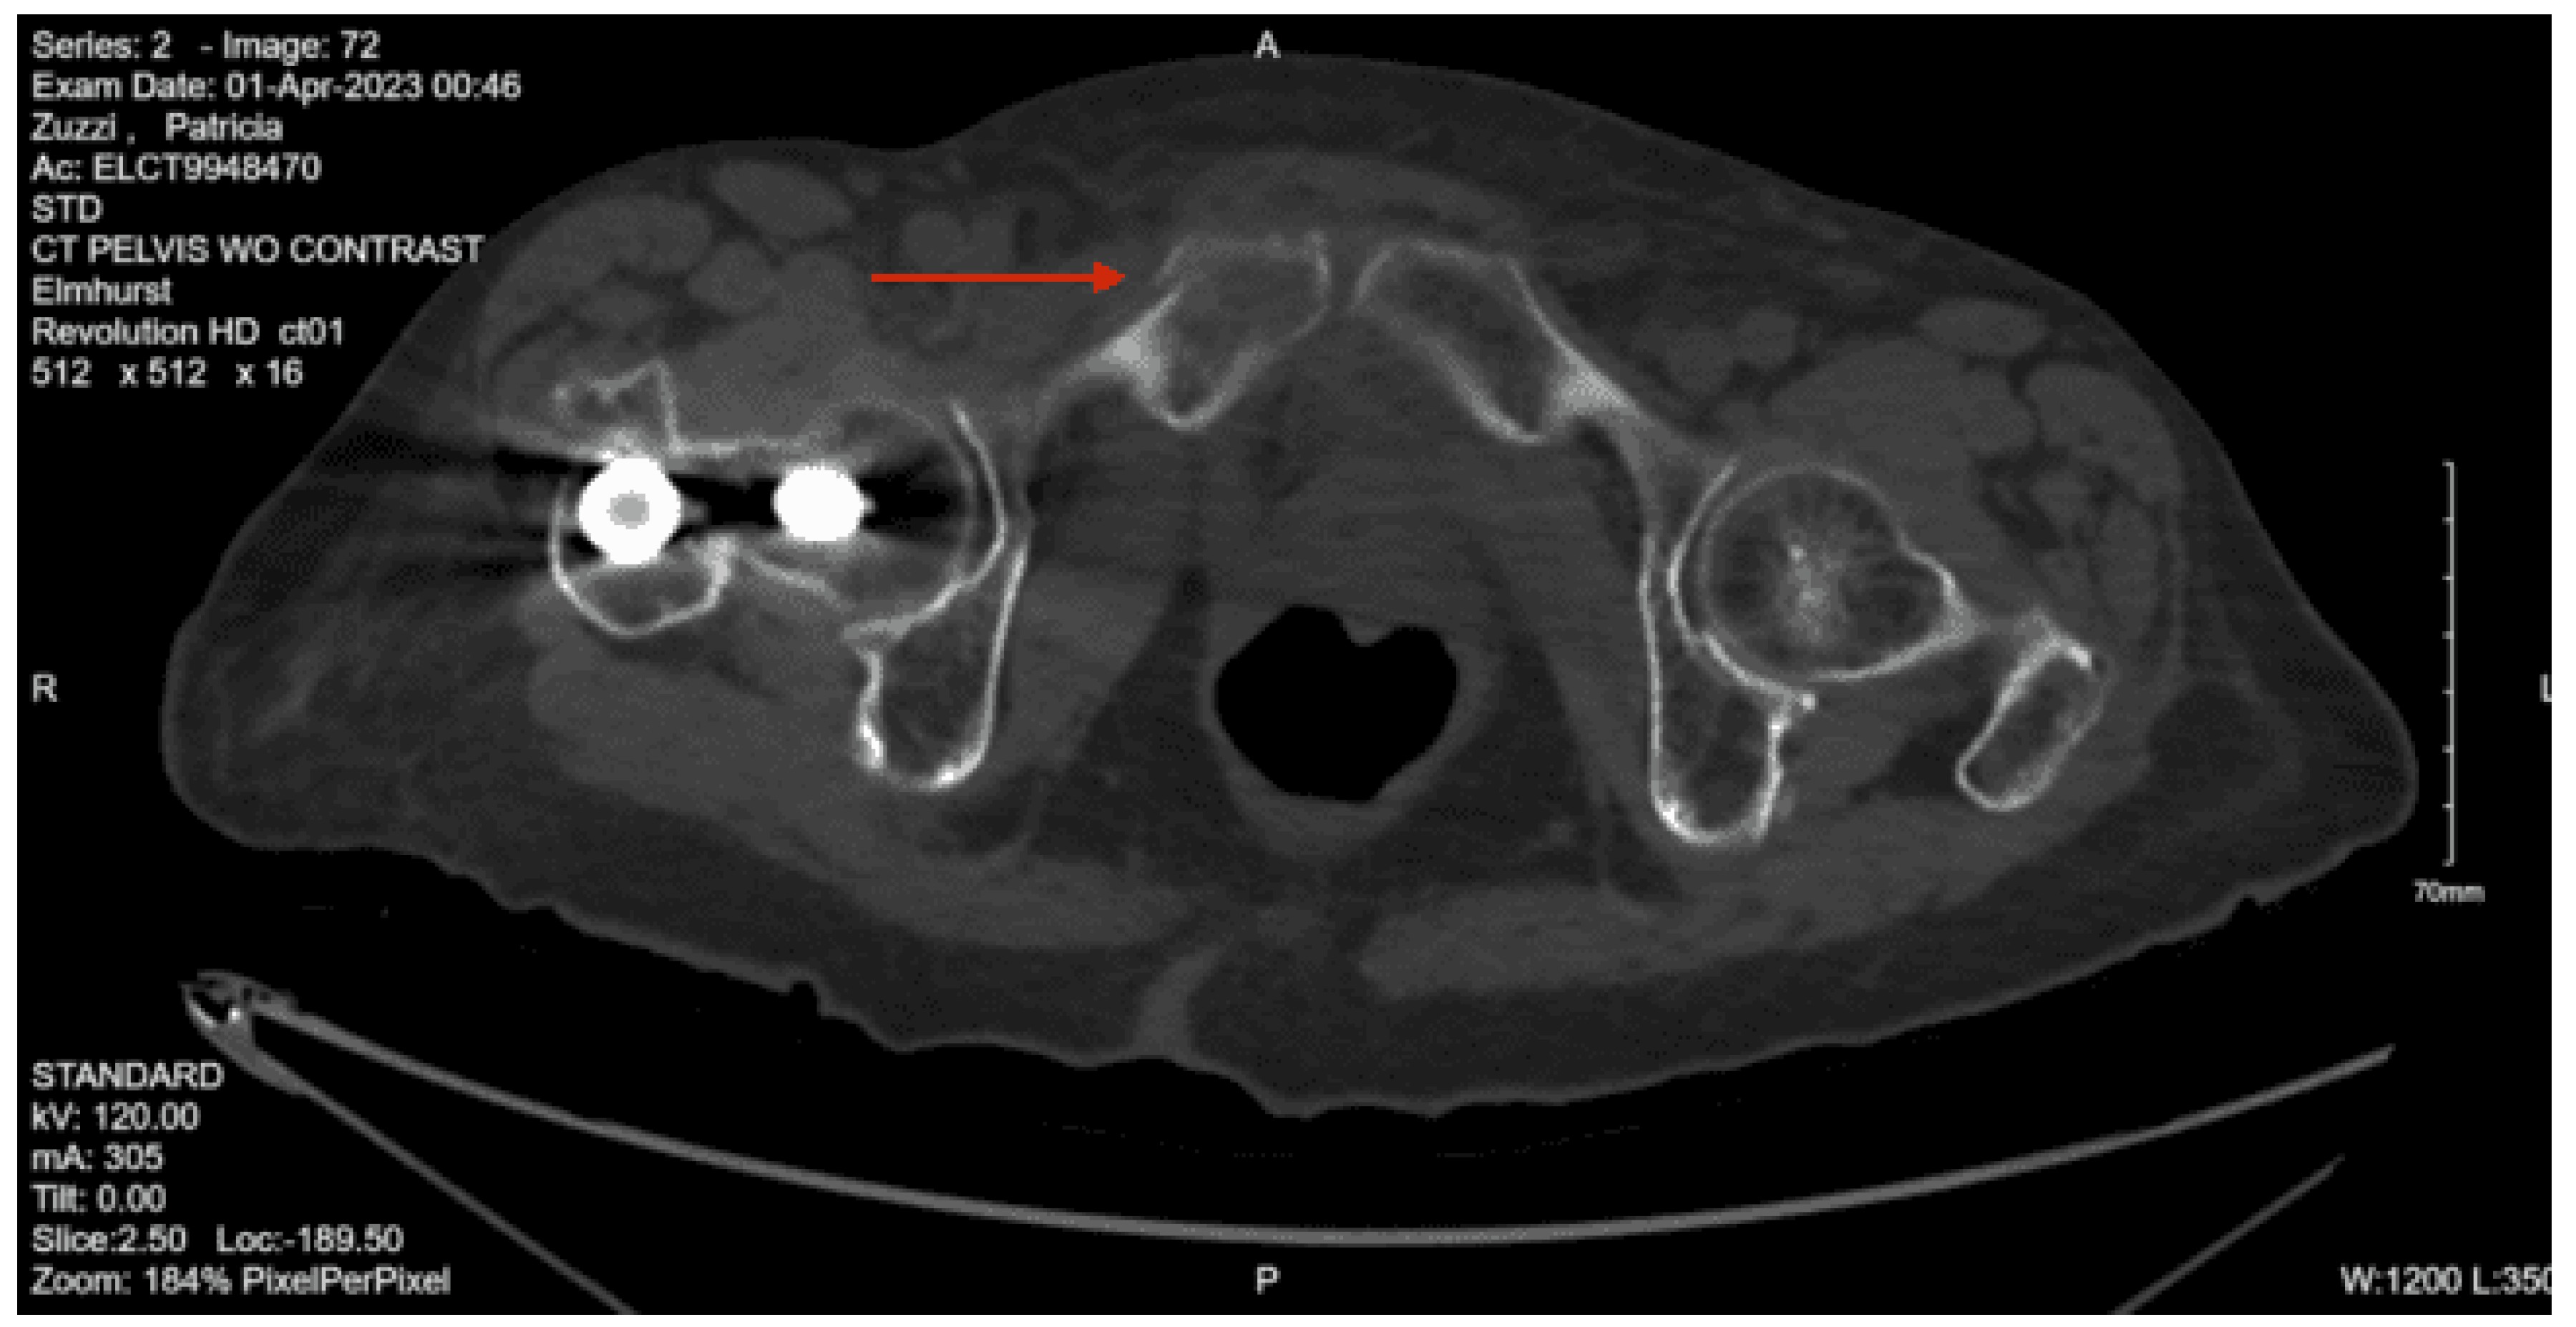

Imaging as shown in Figure 21, Figure 22 and Figure 23:

Portable Pelvis XR: Intact pelvis

CT head non-contrast: Acute subdural hemorrhage over the right cerebral hemisphere measuring up to 12 mm in thickness. There is a mass effect on the right lateral ventricle with a midline shift to the left of approximately 6mm.

CT abdomen/pelvis with contrast: The lumbar spine demonstrates mild degenerative changes at multiple levels. Acute fracture of the superior and inferior pubic rami on the right with associated hematoma. Question: Fracture of the right sacral ala. Infiltrative changes were noted within the right middle lobe. Moderate dilatation of the common bile duct is present. Punctate calcifications are present within the left kidney without obstructive uropathy. There is mild bladder wall thickening consistent with incomplete distention, chronic outflow obstruction, or cystitis. A large amount of stool is present throughout the colon.

CT pelvis non-con: Acute fracture of the right superior and inferior pubic rami with extension through the pubic tubercle in with a small amount of extraperitoneal hemorrhage dissecting through the fascial planes of the anterior pelvis. Question: age-indeterminate fracture of the right sacral ala.